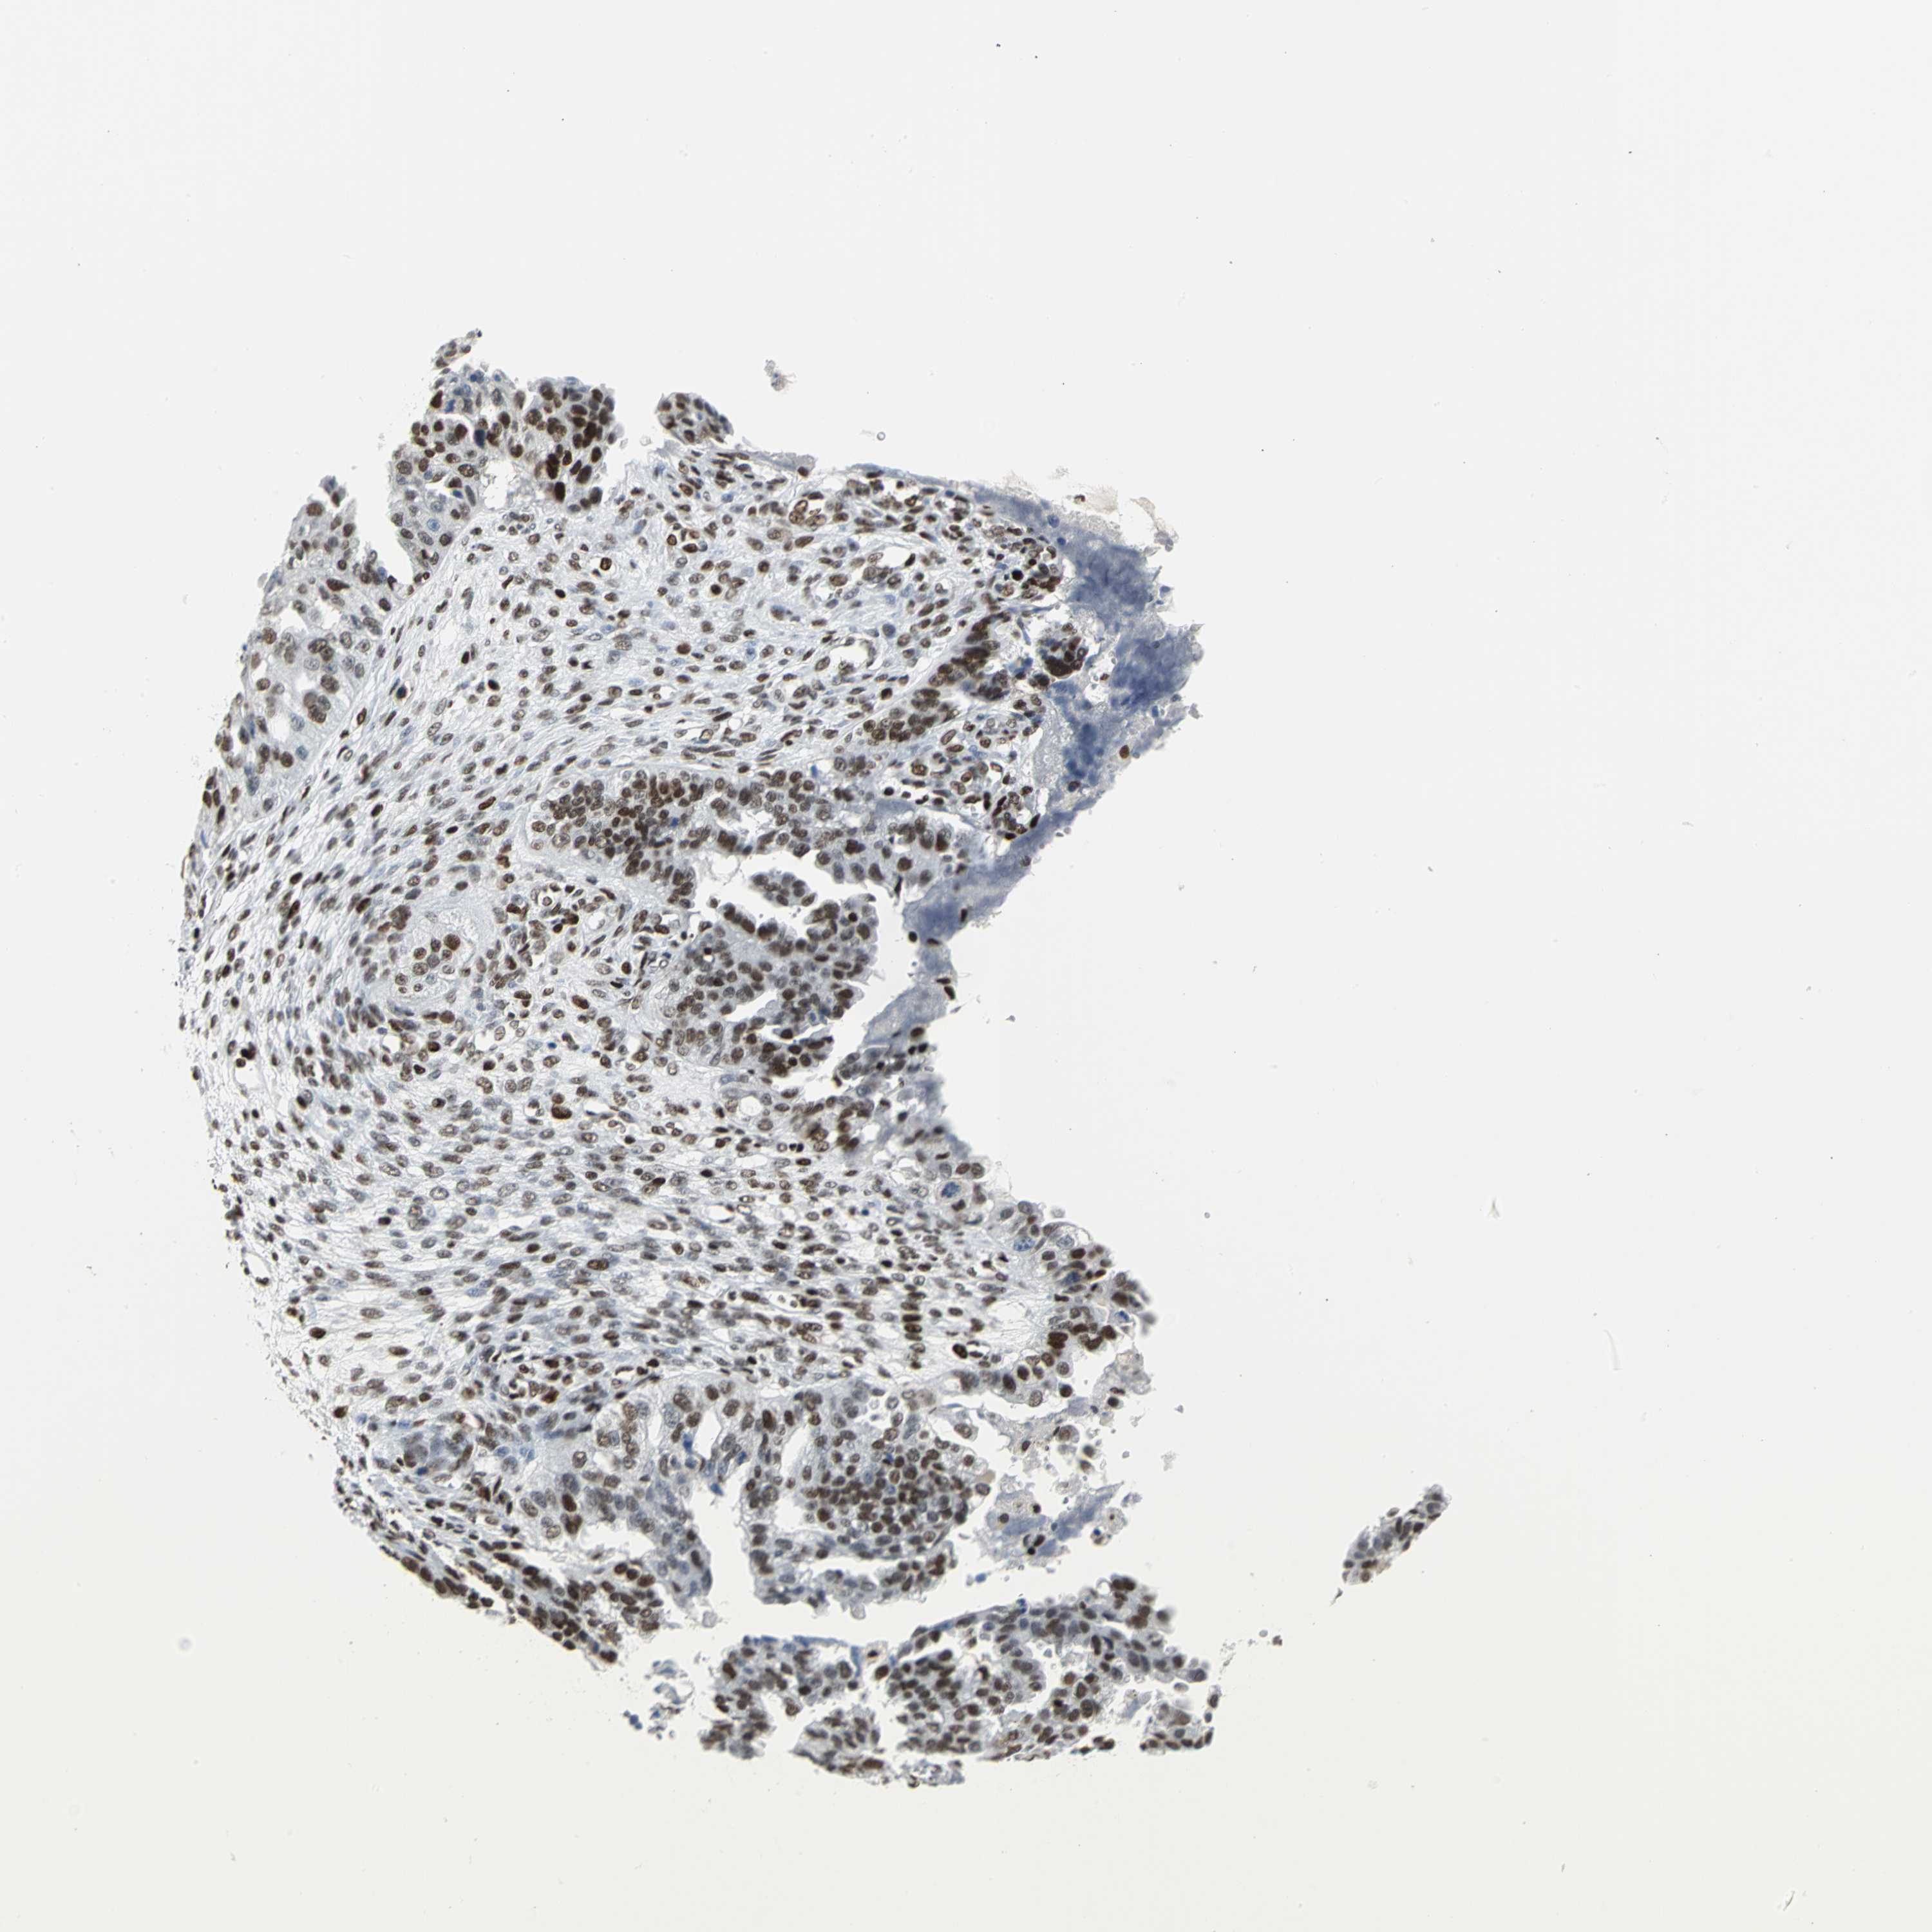

OVARIAN CANCER - Protein expressioni

A mouse-over function shows sample information and annotation data. Click on an image to view it in a full screen mode. Samples can be filtered based on level of antibody staining by selecting one or several of the following categories: high, medium, low and not detected. The assay and annotation is described here.

Note that samples used for immunohistochemistry by the Human Protein Atlas do not correspond to samples in the TCGA dataset.

Antibody stainingi

Antibody staining in the annotated cell types in the current human tissue is reported as not detected, low, medium, or high, based on conventional immunohistochemistry profiling in selected tissues. This score is based on the combination of the staining intensity and fraction of stained cells.

Each image is clickable and will lead to virtual microscopy that enables deeper exploration of all samples and also displays staining intensity scores, fraction scores and subcellular localization as well as patient and tissue information for each sample.

Antibody HPA004911

Staining

High

Medium

Low

Not detected

Intensity

Strong

Moderate

Weak

Negative

Quantity

>75%

75%-25%

<25%

None

Location

Nuclear

Cytoplasmic/membranous

Cytoplasmic/membranous,nuclear

Cystadenocarcinoma, serous, NOS